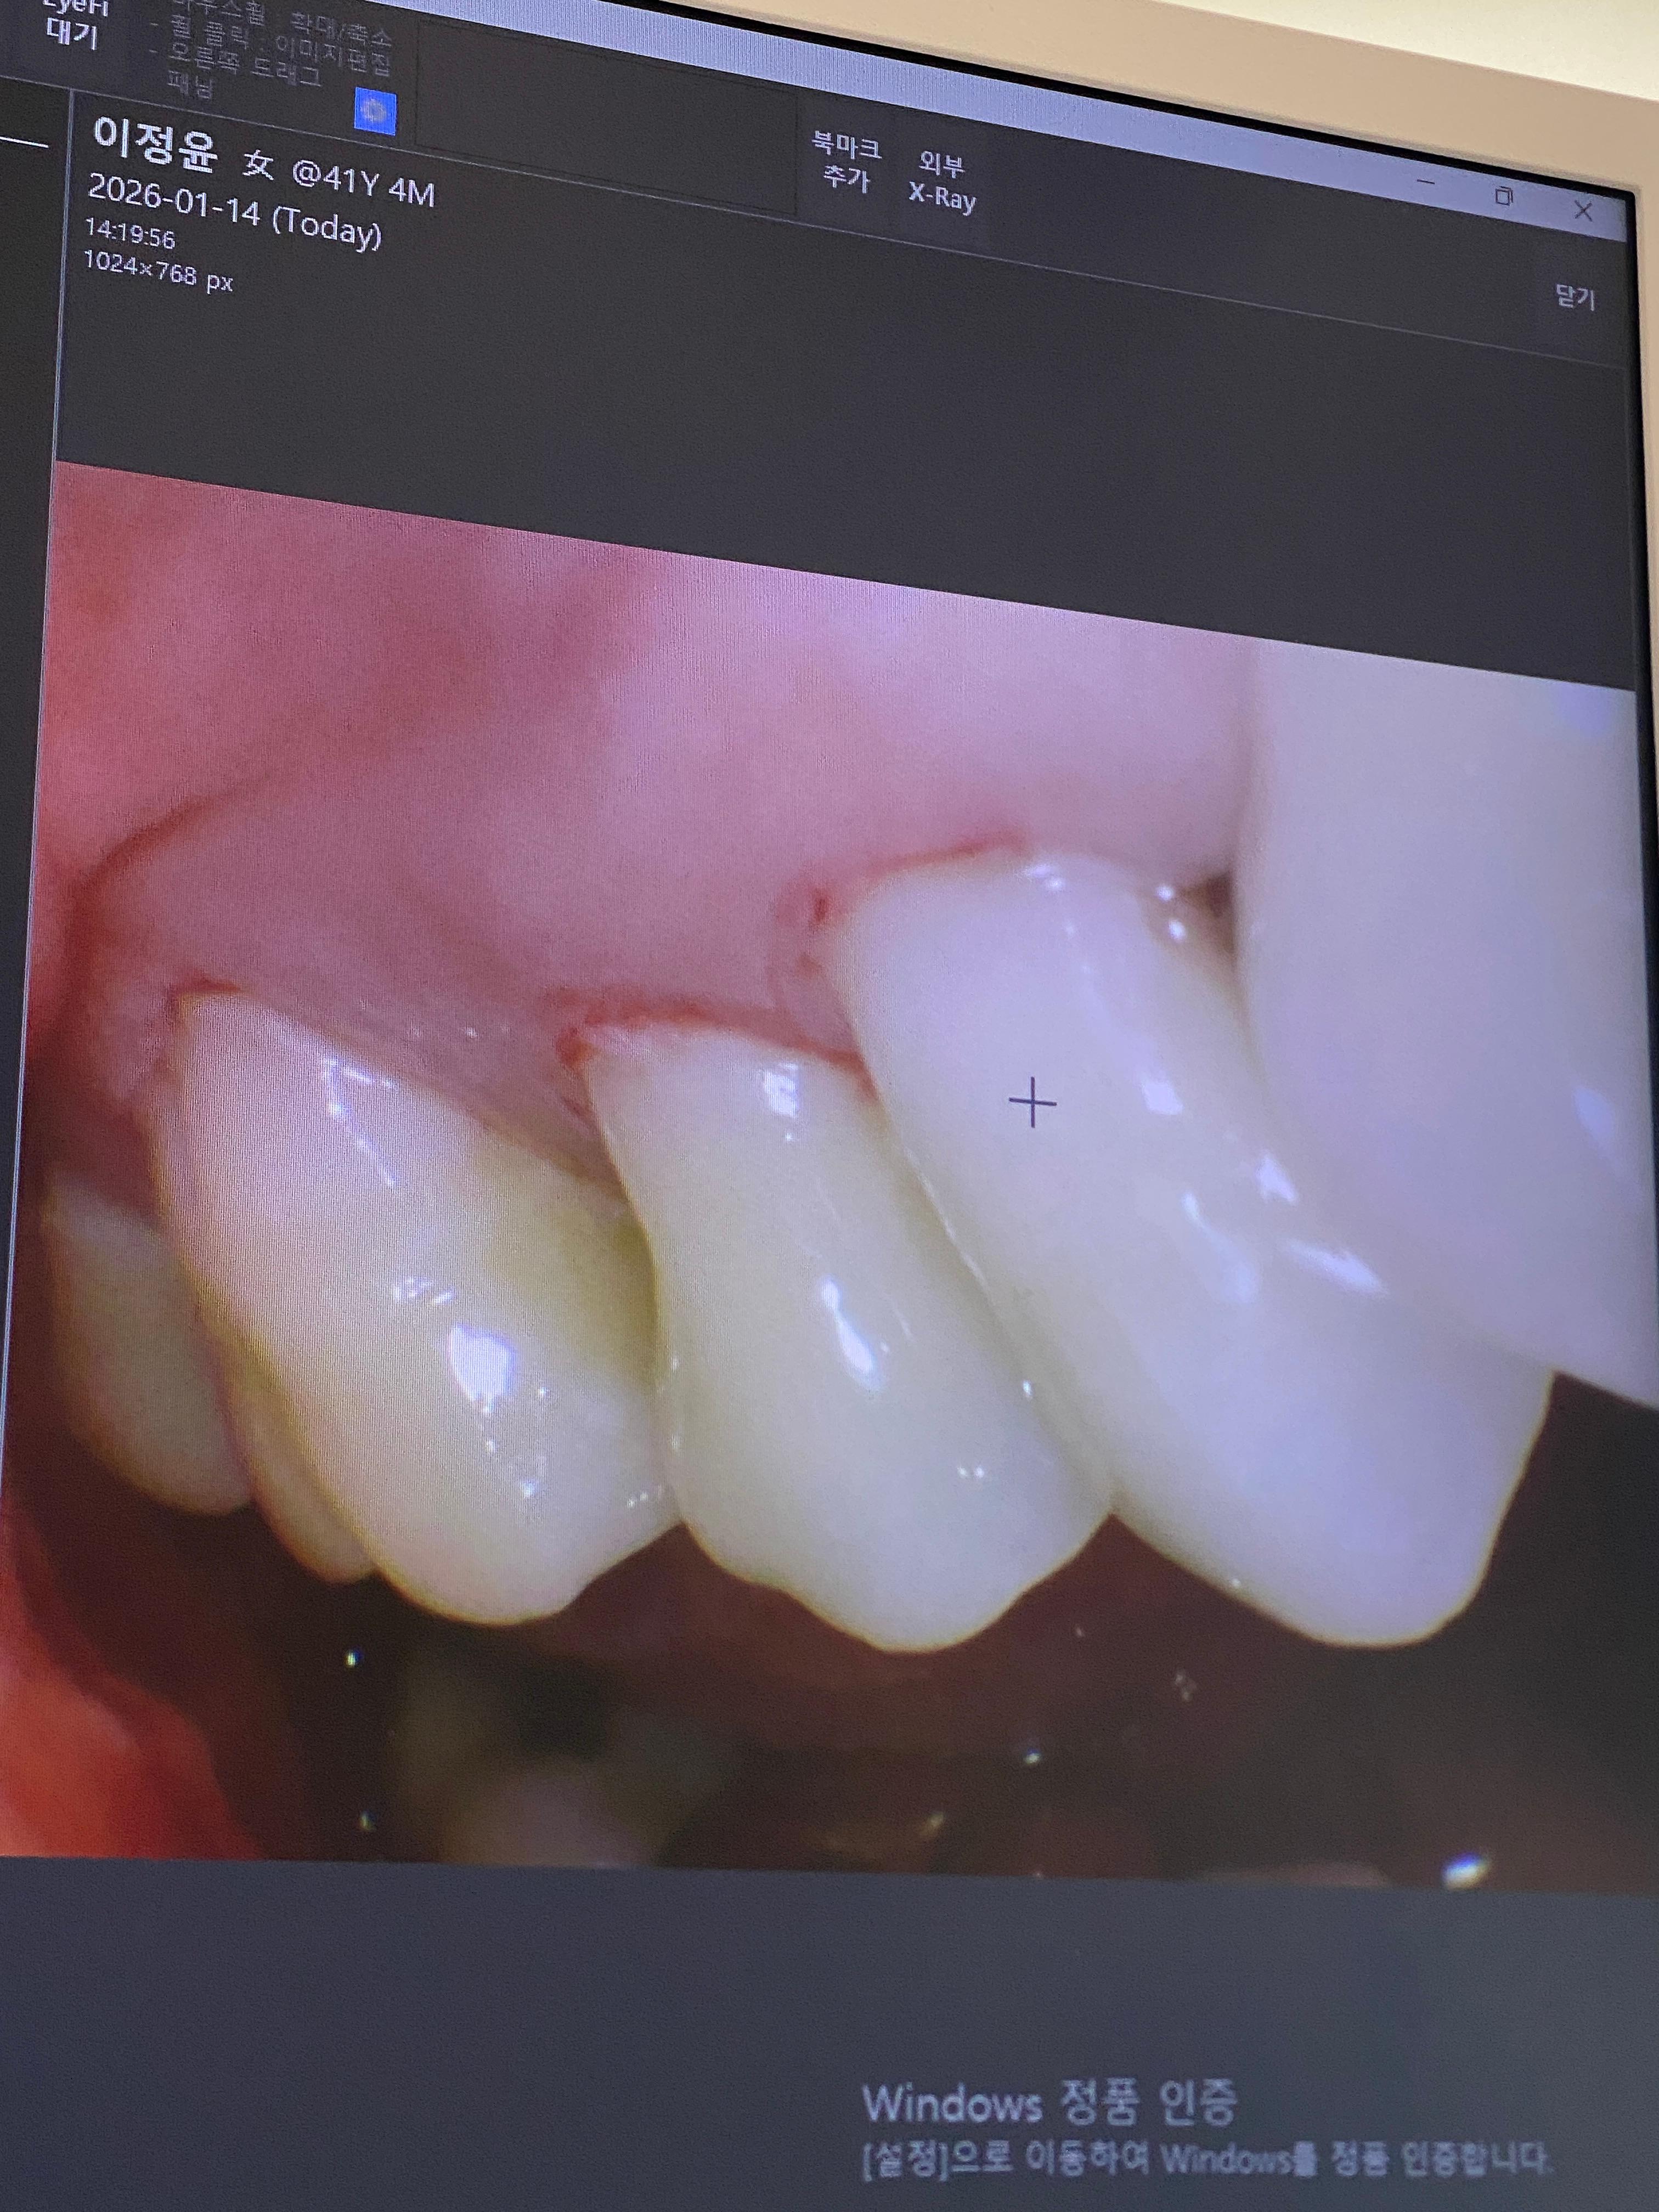

지난주에는 왼쪽 잇몸과 잇몸패임 치료, 이번 주에는 오른쪽 잇몸치료를 진행했습니다.

잇몸치료 후 약을 처방받아 복용했는데, 심한 통증은 없었지만 잇몸이 헐은 듯한 느낌이 있어 양치질을 제대로 하지 못하겠더라고요.

그런데 그 사이에 치석이 쌓였다는 말을 듣고 순간 멍해졌습니다.

원장 선생님께서 치간칫솔이 잘 들어갈 수 있도록 굉장히 신경 써서 치료를 해주셨는데,

마취까지 하면서 치간칫솔이 들어갈 공간을 만들어 준 만큼,

이제는 집에서 얼마나 꾸준히 관리하느냐가 관건인 것 같습니다.